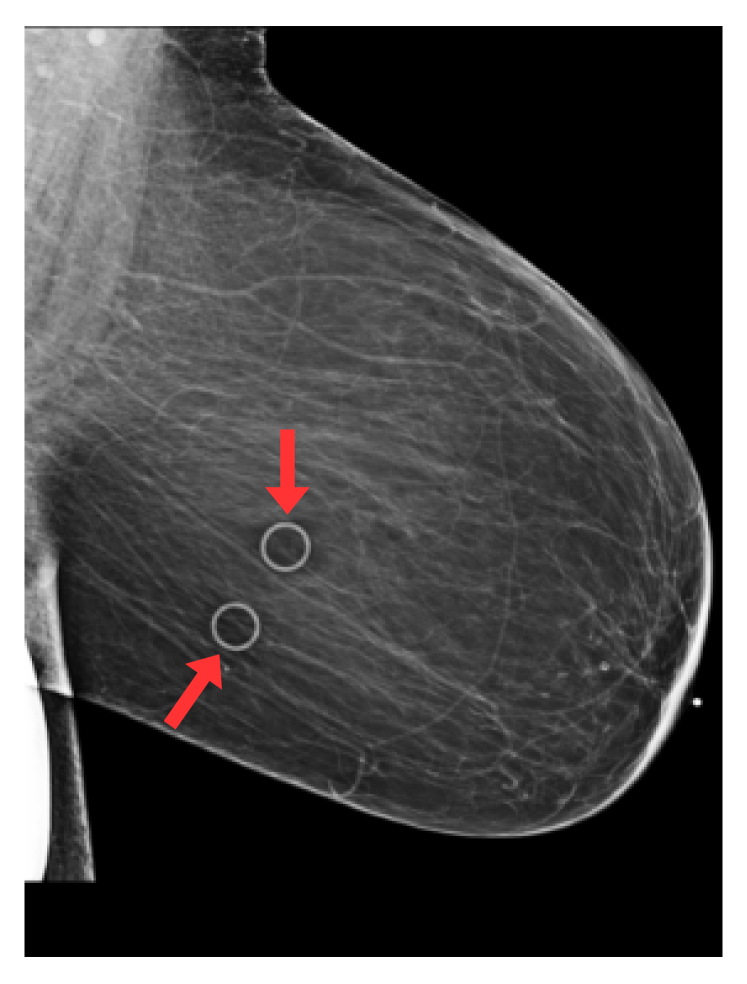

Refer to caption

(a) Circular marker

Fig. 1: Radio-opaque artefacts considered in this study: skin markers (circle and triangles), breast implants, support devices (e.g. pacemakers) and spot compression (or magnification) devices. Red arrows highlight artefacts of interest.

We focus on five types of artefacts: (a) circular skin markers, (b) triangular skin markers, (c) breast implants, (d) devices (e.g. pacemakers), (e) compression and special magnification artefacts. Examples of such artefacts can be found in Fig. 1. Circular and triangular skin markers are radio-opaque markers placed on the breast skin by radiologists at acquisition time [8], indicating locations of moles (circle) or a palpable mass (triangle). Breast implants and devices such as pacemakers or metallic sensors appear as large, very high contrast structures on the mammograms. Similarly, spot compression and special magnification devices are large radio-opaque structures surrounding the breast area, allowing magnification of small, suspicious regions of breast tissue. Despite their clear effect on image appearances, the effect of the presence of such artefacts in mammograms on downstream task models (e.g. breast cancer screening) has - to the best of our knowledge - not been studied so far. This is largely explained by the fact that labels indicating the presence of such artefacts within an image are not typically available in current publicly available mammography datasets.